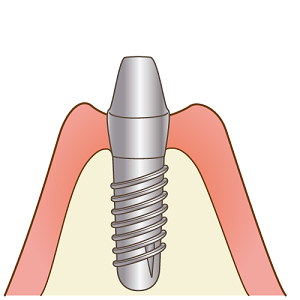

一次手術

インプラントの方向・深さを事前に検査した部分にマーキングします。

インプラントを入れる穴を専用のドリルで開けます。

インプラントを埋め込みます。